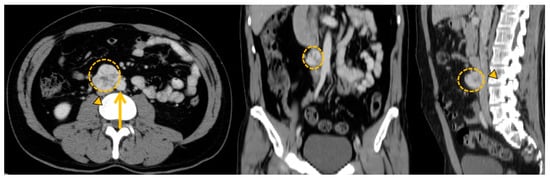

5.2. Curative Surgical Management: How to Prepare a Surgery?

5.3. Palliative Surgery: The Debulking Strategy Concept